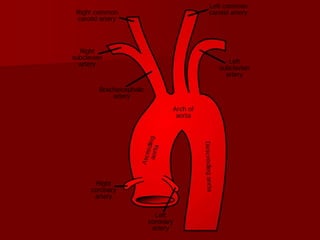

 Blood vessels : aortic arch, subclavian, and

innominate (brachiocephalic) vessels

 Nerves : brachial plexus, left recurrent

laryngeal nerve, spinal cord, sympathetic

trunks

 Respiratory : trachea, apex of the lung

 Digestive : oesophagus

 Lymphatic : thoracic duct on the left

 Thyroid gland.